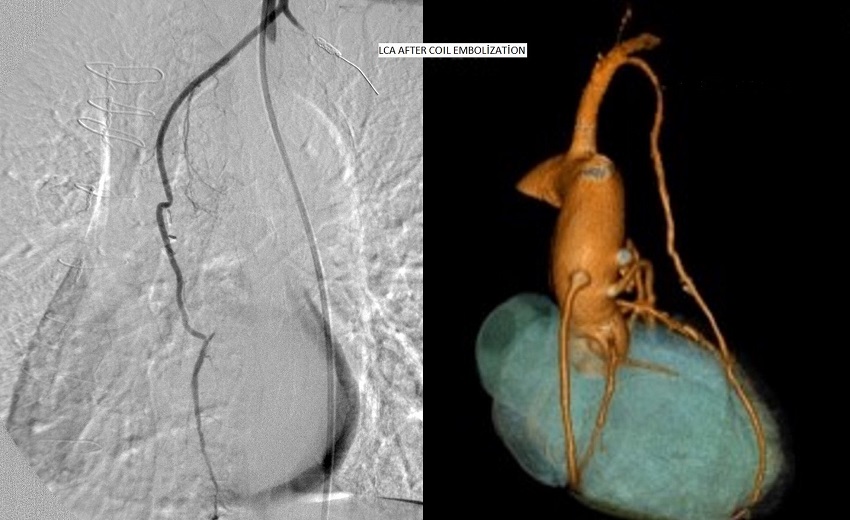

Case 1: 65-year-old female patient, underwent triple CABG three months ago, applied to us with angina pectoris appearing after 50-100 m of walking. She had been under medical treatment of acetylsalicylic acid 100 mg and metoprolol 100 mg. Effort test of the patient whose physical examination and resting electrocardiography (ECG) were normal unveiled ST depression (Table 1). Coronary angiography performed in the patient revealed a well-developed LITA side branch at a distance of 2-2.5 cm from the origin of LITA (Figure 1). The accessory branch, being one and a half times the diameter of LITA, was extending to the lateral thoracic wall, where it was making anastomoses with lateral intercostal arteries and thus supplying blood to anterior and posterior side of the lateral thoracic wall. It was detected that this accessory thoracic artery, the LCA, was stealing a large part of the myocardial blood flow to lateral thoracic wall. The LCA was obliterated via coil embolization (Figure 2). The patient's effort capacity had improved and no ST segment change was observed in the effort test performed one month after the coil embolization of the lateral costal artery.

Case 2: 56-year-old female patient expressed unstable angina pectoris and dyspnea within the first week after CABG. Transthoracic ECG revealed left ventricular free wall motion abnormality and 1-2 mitral valve regurgitation. Ejection fraction was 30-35% (Table 1). Coronary angiography was performed in the patient who has been under medical treatment for diabetes mellitus for 15 years. It exposed the LCA which arose from the LITA at a distance of 2-2.5 cm from the origin of LITA. It was extending to the 6th intercostal space and was two thirds the diameter of the LITA. It was postulated that the LCA had aggravated the steal phenomenon, therefore it was obliterated via coil embolization. After LCA obliteration, the patient's angina disappeared, but dyspnea persisted. Since she had advanced restrictive lung disease, she referred to a pulmonologist with medical treatment comprising of acetylsalicylic acid 100 mg, metoprolol 100 mg, spironolactone 50 mg and hydrochlorothiazide 50 mg.

Case 3: 71-year-old male patient, underwent triple CABG one month ago, applied to our emergency department with unstable angina pectoris. His ECG record displayed ST segment elevation and troponin-T value was measured 0.45 ng/ml (Table 1). In primary percutaneous coronary intervention, it was detected that the left subclavian artery (SCA) was proximally occluded, the LITA graft was patent, and there was a LITA side branch, thought to be the LCA, which was one third the diameter of the LITA. The LCA was extending to the 6th rib and making anastomoses with intercostal arteries. First, balloon angioplasty was performed in the left SCA. Then, the lesion causing 80% left anterior descending artery (LAD) stenosis was stented. After that, the LCA was obliterated via coil embolization. Finally, the left SCA was stented. Stent placed in the SCA also occluded the LITA ostium inadvertently. The patient, being hemodynamically stable, was discharged from the hospital a week after admission with a medical treatment comprising of acetylsalicylic acid mg and metoprolol 100 mg. In follow-up visits, cardiac parameters have been found to be normal.

A study conducted on cadavers demonstrated that the LCA shows variation at the proximal part of the LITA (15%)[6]. It could be present unilaterally or bilaterally, and it has a diameter close to the LITA. The same study pointed out the increased possibility of steal phenomenon due to these side branches in case the LITA was used as a vascular graft for the coronary revascularization[6]. Henriquez-Pino et al.[6] showed that the LITA arises directly from the left SCA in 70% of the cadavers and that the internal thoracic artery gives LAC branch more distally on the left side. Other arteries accompanying the LCA at the proximal part of the LITA are the suprascapular artery, transverse cervical artery, inferior thyroidal artery, and ascending cervical artery. In the all three cases we present, the LCAs of varying diameter were anastomosing with lateral intercostal arteries. We have detected the undivided LCA in only three cases within seven years. In a long period of follow-up, due to probability of existence of asymptomatic patients and symptomatic patients applying to other institutions, the exact rate of prevalence of undivided LCA for our center couldn't be determined. In one of our cases, a female with breast-feeding history, LCA diameter was greater than the LITA diameter (Figure 1). After evaluating the coronary angiographies of 103 patients who underwent CABG surgery, Sutherland et al.[10] found that the LCA was present in 30 (29%) patients, either unilaterally or bilaterally. They showed that 25 of these were extending to the 2nd intercostal space, while the remaining 5 extended to the 5th intercostal space.